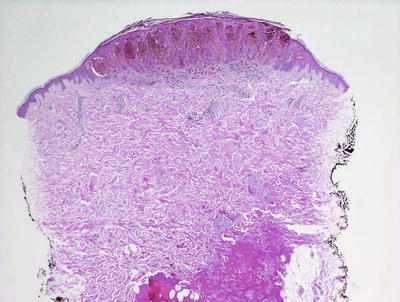

Fig. 20.31

A Spitz nevus is characterized by a sharply-circumscribed proliferation of large nests of intraepidermal and dermal melanocytes with abundant cytoplasm